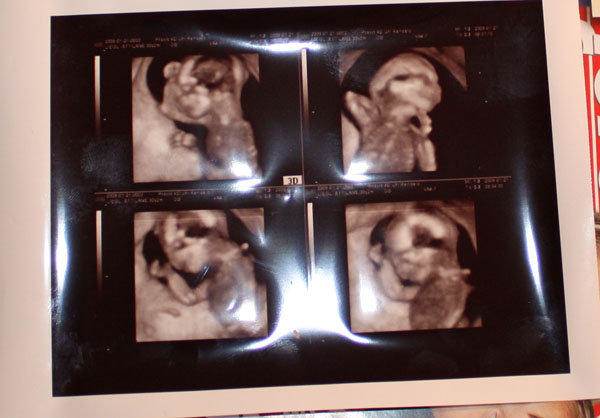

Megjöttünk, az uh-ról, nem tudtam előbb jönni, mert főznöm kellett.

Szóval minden rendben van. Képzeljétek el először oldalt feküdt, utána hanyadt vágta magát, és az egyik kezét a feje alá tette, utána a másik kezével matatott. Aztán a másik kezét is a feje alá tette. Utána meg a fejét felemelte és az egyik kezével az állát fogta a másik meg a feje alatt volt. Annyira jó volt nézni, hogy el sem hiszitek. És annyira érdekes hogy már ilyen picikén ilyeneket csinál. Még a könnyem is kicsordult. Van fénykép is, csa a szkennelt apa lehúzta úgy hogy egyenlőre csak lefotózni tudtam.

Még apa is elérzékenyült.

Méretei: BPD 40 mm

HC 14 cm

OFD 48,6 mm

FL 2,37 cm

AC 11,86 cm

Kb 15-20 cm között van, és 20 g a drágám. Na és KISLÁNY

Nagyon jók a képek,nekem a felsök közül a jobboldali tetszik nagyon!

Már én is nagyon várom a 4dt,február 13-án megyünk akkor leszek 20 hetes!

De most még jobban meghatódtam, mert annyira érdekes és csodálatos volt hogy ilyeneket tud csinálni már most amikor ennyire picike. Hisz kb 15-20 cm között van és 20 dkg.